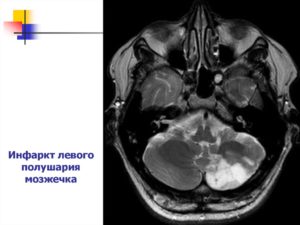

Острые нарушения кровообращения в мозжечке составляют инфаркты (некроз) либо кровоизлияния, которые имеют схожие механизмы развития с другими формами внутримозговых инсультов, поэтому факторы риска и основные причины будут совпадать. Патология встречается у людей среднего и пожилого возраста, чаще обнаруживается среди мужчин.

На долю инфаркта мозжечка приходится около 1,5% всех внутримозговых некрозов, в то время как кровоизлияния составляют десятую часть всех гематом. Среди инсультов именно мозжечковой локализации примерно ¾ приходится на инфаркты. Смертность высока и в иных случаях превышает 30%.